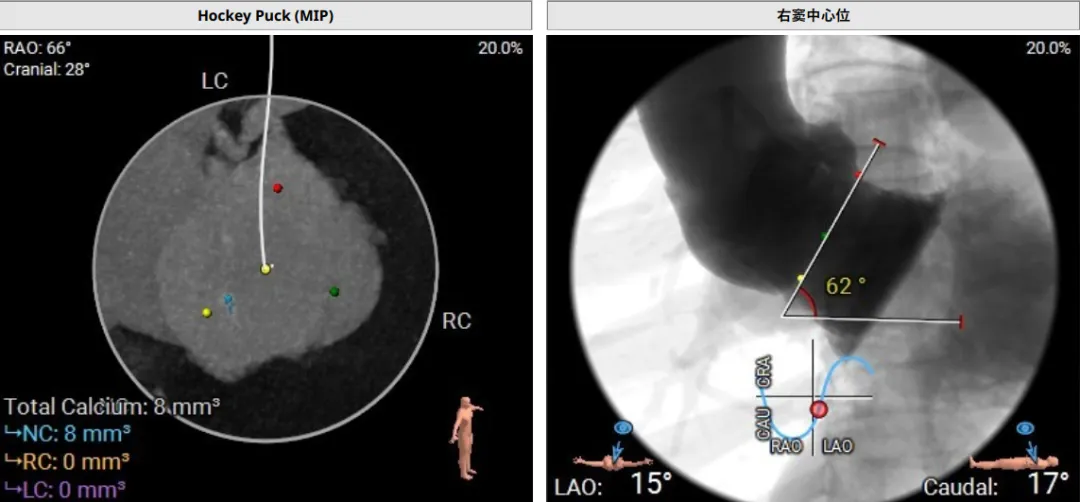

该患者术前CT评估提示:主动脉瓣Type-I型,瓣叶稍增厚,左右冠窦瓣叶交界粘连,无冠窦瓣叶轻微钙化,存在三个瓣窦,分布不均匀,左右冠窦融合;主动脉瓣环周长折算直径32.6mm;左心室流出道周长折算直径32.0mm,无钙化,无狭窄;STJ直径36.2mm,升主动脉直径38.6mm;左侧冠脉10.4mm ,瓣叶长10.8mm;右侧冠脉18.7mm,瓣叶长11.2mm;双侧冠脉开口高度可,无钙化;心尖-主动脉夹角偏大,左室主动脉夹角为120°;

手术过程中,团队严格按照标准操作流程实施。自介入器械导入至瓣膜释放完成,器械用时约10钟。整个过程中,手术团队通过右冠窦居中造影、定位件入窦确认、释放后联合超声与造影评估,确保了瓣膜定位精准、释放平稳。术中超声评估显示无瓣周漏,血流动力学表现良好,手术过程顺利。

调整角度后造影,右窦居中位置